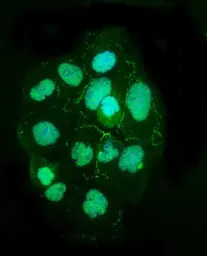

ICC/IF analysis of A431 cells using GTX03355 TJP2 antibody. Enzyme antigen retrieval was performed using IHC enzyme antigen retrieval reagent for 15 mins.

Green : Primary antibody

Blue : DAPI

Dilution : 5μg/mL